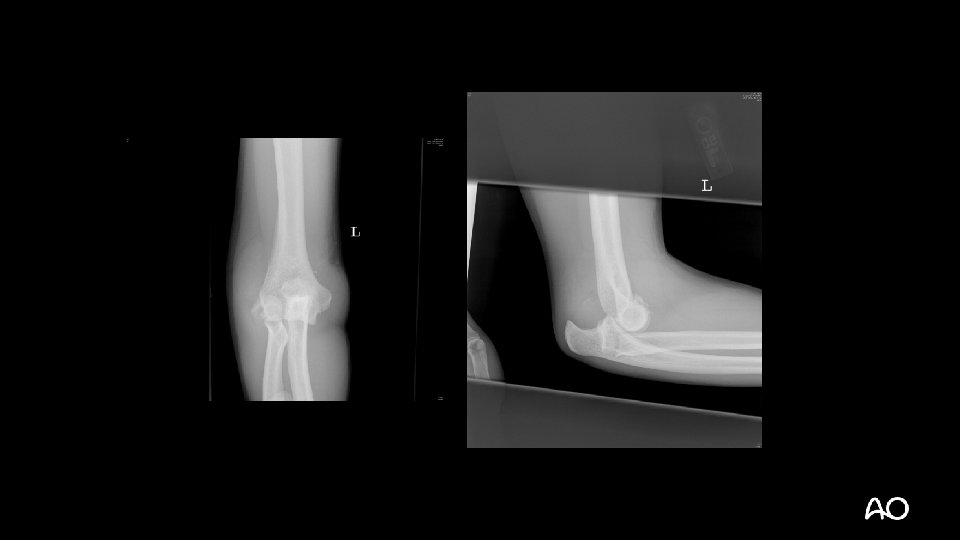

Transolecranon fracture dislocation • Not a simple olecranon fracture • Do not treat with tension band wiring • Olecranon fracture with ANTERIOR dislocation but intact proximal radioulnar joint • Ligaments may be intact

Transolecranon—tactic • Extensile posterior exposure • Full-thickness cutaneous flaps: • Can access Kocher (ECUanconeus) interval for radial head repair/replacement if necessary

Transolecranon—tactic • Address coronoid fractures through olecranon fracture line • Anatomically reduce olecranon • Plate-and-screw constructs are often necessary (no tension band) • Normally, ligaments are relatively spared